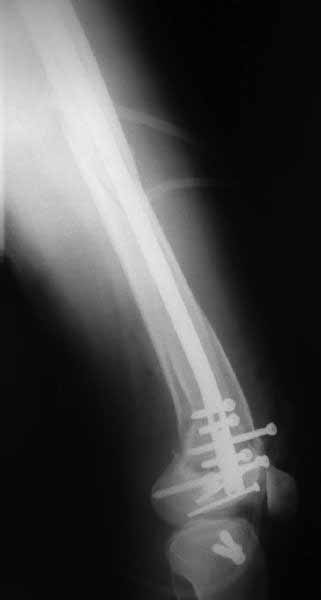

Ответ на эту часть Вашего поста – вложенный файл. Больная оперирована неделю назад по поводу открытого перелома дистального эпиметафиза бедренной кости. После операции она идёт в рентгенкабинет для выполнения послеоперационной контрольной рентгенографии, представленной на слайдах 10 и 11. Узнав, почему её фотографируют, просила передать Вам, Антон, привет.